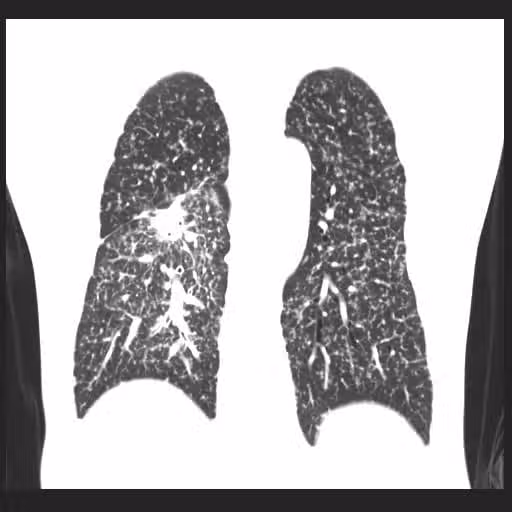

圖片來源:蘇一峰臉書

蘇一峰表示,該病人平常熱愛運動、跑馬拉松,而且不菸不酒,從外表看來精神飽滿、體力很好,但其實,台灣有六成的肺癌患者,本身都沒有抽菸習慣,更該受到重視的,其實是二手菸、煮菜油煙、馬路空汙等危險因子,如果排除上述因素,就有可能和「家族遺傳」有關…不少病人都是家人確診後,連帶著也檢查發現。